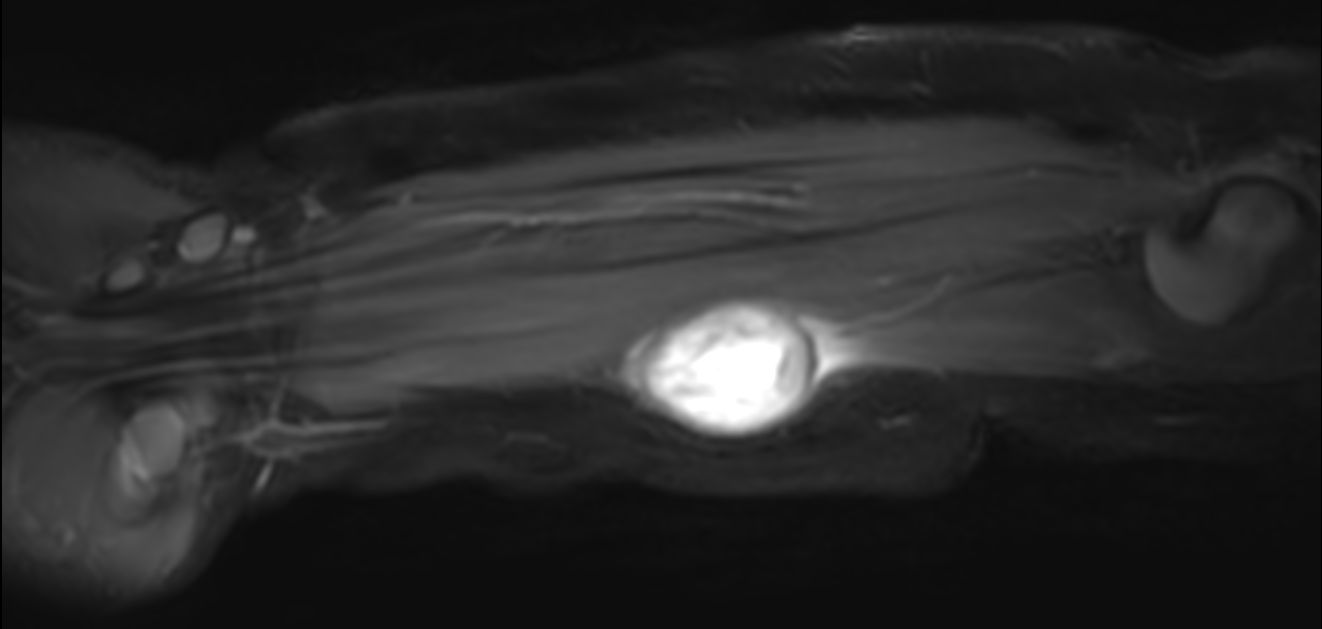

Pediatric forearm with lesion

Pediatric patient with a lesion in the forearm. mDIXON XD provides uniform fat-free imaging and allows for multiple image types in one single scan. Integration of Compressed SENSE acceleration technique enables speeding up of the entire exam.

Coronal T2w mDIXON XD (In Phase)Compressed SENSE

Coronal T2w mDIXON XD (Water only)Compressed SENSE

Sagittal T2w mDIXON XD (In Phase)Compressed SENSE

Sagittal T2w mDIXON XD (Water only)Compressed SENSE